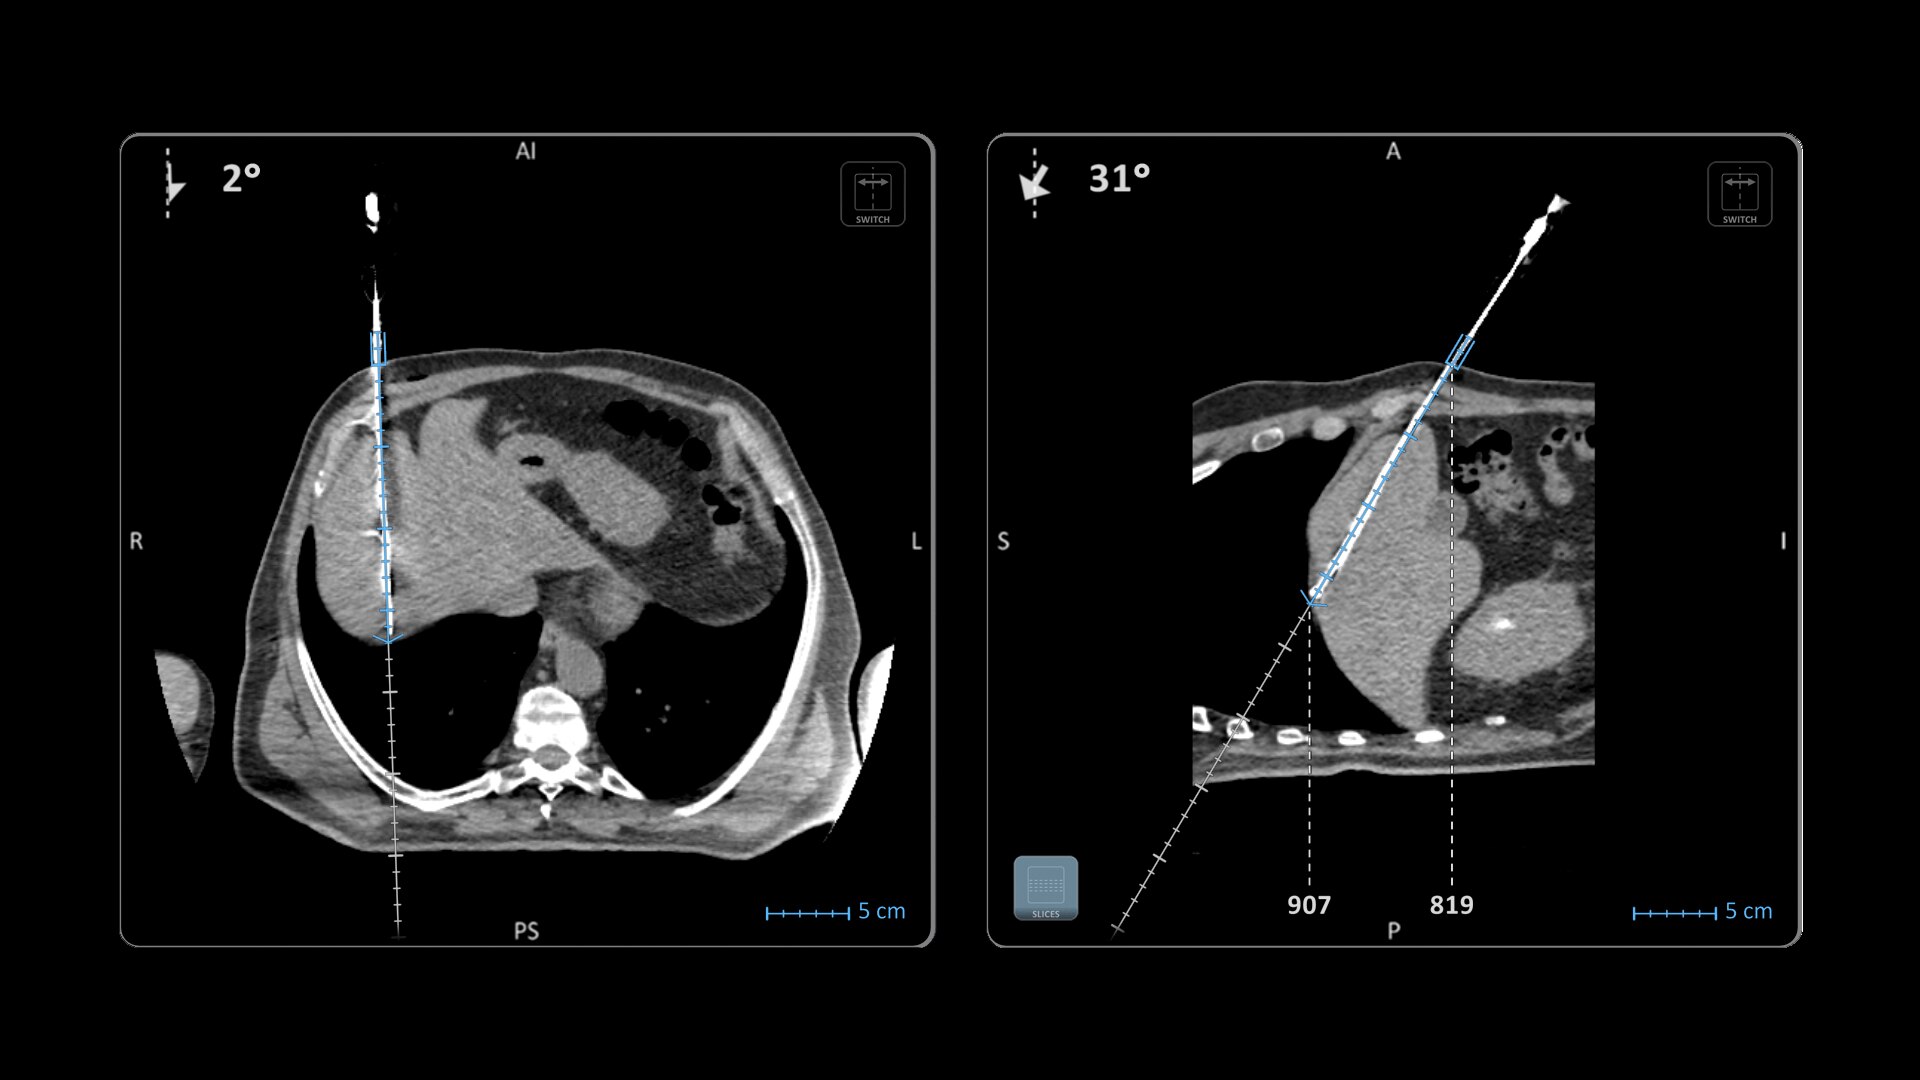

Imactis® CT-Navigation™

Planning and navigation solution for interventional percutaneous radiology.

Improve accuracy to reach target and avoid critical structures and organs¹

Ideal to use with various percutaneous interventions² with various complexity

Imactis® CT-Navigation™ is an electromagnetic (EM) navigation solution for CT-guided percutaneous procedures

Imactis® CT-Navigation™ is designed to radically improve efficiency of Interventional procedures for clinicians and hospitals by increasing their accuracy.